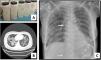

We present a series of three consecutive cases of extracorporeal membrane oxygenation (ECMO) support to perform WLL in patients at risk of complications.Case 1 A 71-year-old woman consulted for worsening dyspnea and supplement oxygen therapy requirement. An interstitial pattern in chest radiography was noted and severe primary PAP diagnosis confirmed by core needle biopsy. Pulmonary function tests showed a restrictive pattern with moderate decrease in diffusion capacity (forced vital capacity [FVC] 1674 mL [72% of predicted value], forced expiratory volume [FEV1] 1575 mL [87%], FEV1/FVC 94%, diffusing capacity of the lung for carbon monoxide [DLCO] 56%, total lung capacity [TLC] 81%). A first WLL was attempted, complicated with progressive respiratory worsening and cardiorespiratory arrest. Procedure was rescheduled after stabilization to be carried out under respiratory support with veno-venous extracorporeal membrane oxygenation (V-V ECMO). After anesthetic induction and intubation with double-lumen endotracheal tube, V-V ECMO was implanted (drainage cannula through left femoral vein [21F] and return cannula through right jugular vein [17F]) (Maquet Cardiopulmonary GmbH, Rastatt, Germany) and maintained with these parameters: flow 3 L/min with FiO2 = 1 and sweep gas of 3 L/min. WLL procedure was completed in a single session by instilling 10 L of saline (1 L aliquots at 37 °C) (Fig. 1A). Ultraprotective ventilation was carried out (volume-limited assist control ventilation with tidal volume 190 mL, respiratory rate 12 bpm, positive end-expiratory pressure [PEEP] 10 cmH2O, FiO2 = 0.9), and no hemodynamic instability occurred. Clinical improvement was observed at 48 h achieving V-V ECMO weaning. Patient was extubated at 72 h and discharged 9 days later, with oxygen discontinuation and radiological improvement. A. Characteristic fluid extracted during WLL, initially with a milky appearance and progressive clearing. B. High-resolution chest CT. Lung parenchyma with extensive ground-glass opacities and associated septal thickening (typical “crazy paving” pattern). C. Chest radiograph. Extensive bilateral alveolointerstitial infiltrates; ECMO cannulae (arrows) properly positioned, with separation >10 cm to minimize recirculation phenomenon. A 35-year-old woman, former smoker, was admitted for progressive dyspnea and respiratory failure. High-resolution chest computed tomography (CT) found extensive “crazy paving” foci suggestive of PAP (Fig. 1B); bronchoalveolar lavage and transbronchial biopsy confirmed the diagnosis. Respiratory function tests showed a normal spirometric pattern with moderately decreased diffusion (FVC 2890 mL [90%], FEV1 2650 mL [98%], FEV1/FVC 92%, DLCO 54%). WLL procedure was scheduled under V-V ECMO. Introducer sheaths were placed in both femoral veins under local anesthesia and sedation, prior to anesthetic induction; after that ECMO was implanted (23F left femoral drainage cannula, 17F right femoral tip-perforated 50-cm return cannula). Extracorporeal support (flow 3 L/min with FiO2 = 1 and sweep gas 2 L/min) and protective one-lung ventilation (volume-limited assist control ventilation with tidal volume 150 mL, respiratory rate 15 bpm, PEEP 8 cmH2O, FiO2 = 0.5) via double-lumen tube were started, performing bilateral lung lavage with saline at 37 °C, through 10 aliquots of 900 mL in each lung. ECMO weaning was attained 12 h later and extubation 48 h after the procedure. ICU stay was 3 days, being discharged home 10 days after the WLL without the need for home oxygen therapy. A 51-year-old woman with previous diagnosis of PAP required ICU admission with respiratory failure. Respiratory function tests presented mild restrictive pattern and severe diffusion impairment (FVC 1570 mL [62%], FEV1 1539 mL [71%], FEV1/FVC 97%, DLCO 28%, TLC 76%). Anesthetic induction with double-lumen tube intubation was performed, prior to implantation of ECMO cannulae (21F drainage cannula through left femoral vein and 50 cm tip-perforated 17 F return cannula through right femoral vein) (Fig. 1C). ECMO parameters were flow 2.6 L/min with FiO2 = 1 and sweep gas 2 L/min. Ultra-protective mechanical ventilation parameters were established (pressure-limited assist control ventilation, maintaining a driving pressure of 10 cmH2O and initial PEEP of 5 cmH2O), and WLL was performed with 10 aliquots of 800 mL in each lung. The procedure was uneventful, achieving ECMO support weaning and extubation 48 h after the procedure. The ICU stay was 5 days, and she was discharged home 8 days after the WLL, without chronic oxygen therapy requirements.